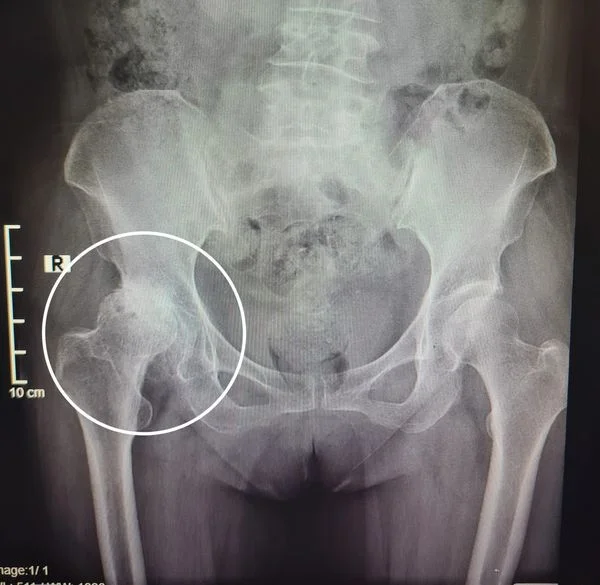

HOẠI TỬ CHỎM XƯƠNG ĐÙI CÓ NGUY HIỂM KHÔNG?

Hoại tử chỏm xương đùi đang có xu hướng tăng nhanh và trẻ hóa độ tuổi mắc bệnh. Là căn bệnh nguy hiểm nguy cơ dẫn đến tàn tật cho người mắc bệnh nhưng...